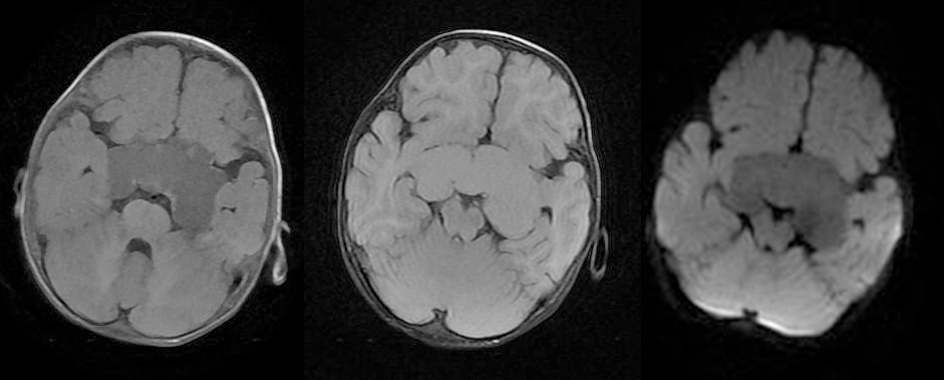

男,5 岁。反复呕吐伴头围增大半月余。CT 显示蛋壳样钙化。MR-T1W 囊液呈稍高信号,T2W 呈高信号,DWI 低信号,增强扫描可见囊壁强化,局部可见结节样强化。 医学百科网 | YxBaike.Com